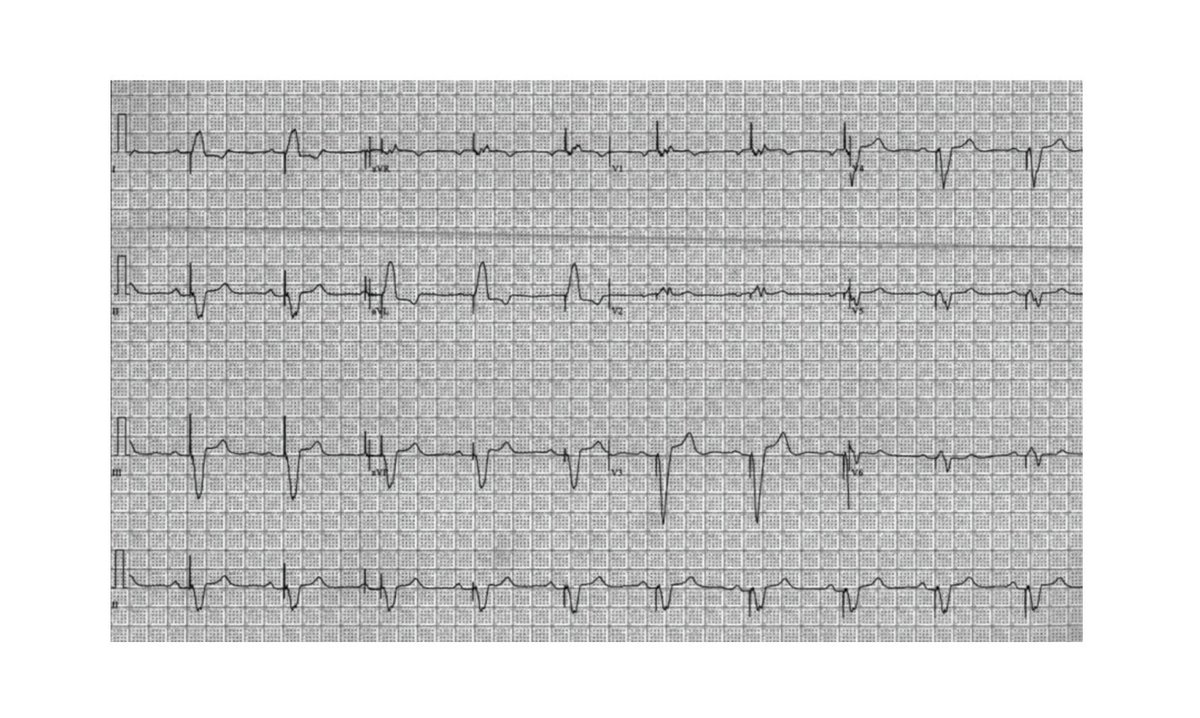

hmpgloballearningnetwork.com/site/eplab/cas… Tremendously humbled by the privilege of sharing our #leadlesspacemaker experience with @EPLabDigest! We live in interesting times 😁 Kudos to the team at @MedStarWHC for their work with this provocative case study with #Aveir